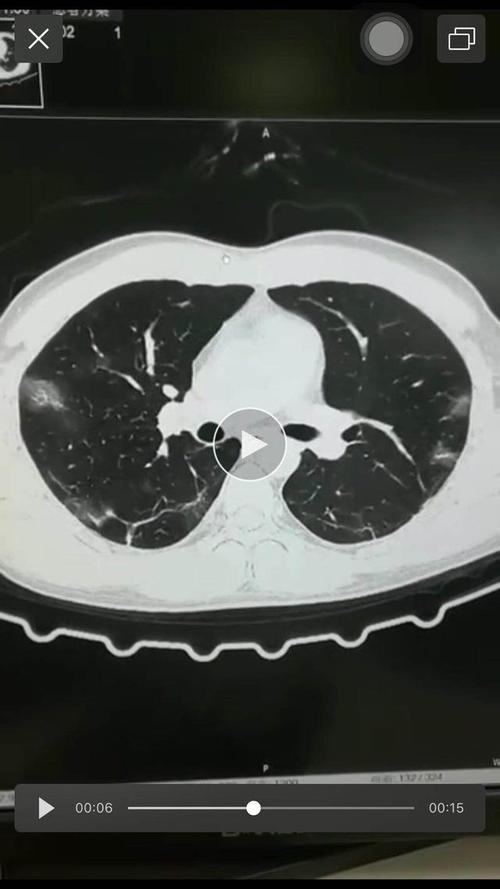

新冠肺炎肺部影像

新冠肺炎肺部影像,新冠肺炎

新冠肺炎的影像学表现小结

因为大众已了解到,新冠病毒感染后肺部ct会出现斑片状磨玻璃影

新冠肺炎(来自丁香园))

新冠肺炎感染后,患者的肺是什么样的?专家:这种最可怕

其它 阅图识病之新冠肺炎一例 写美篇 影像所示: 双肺可见多发大小不